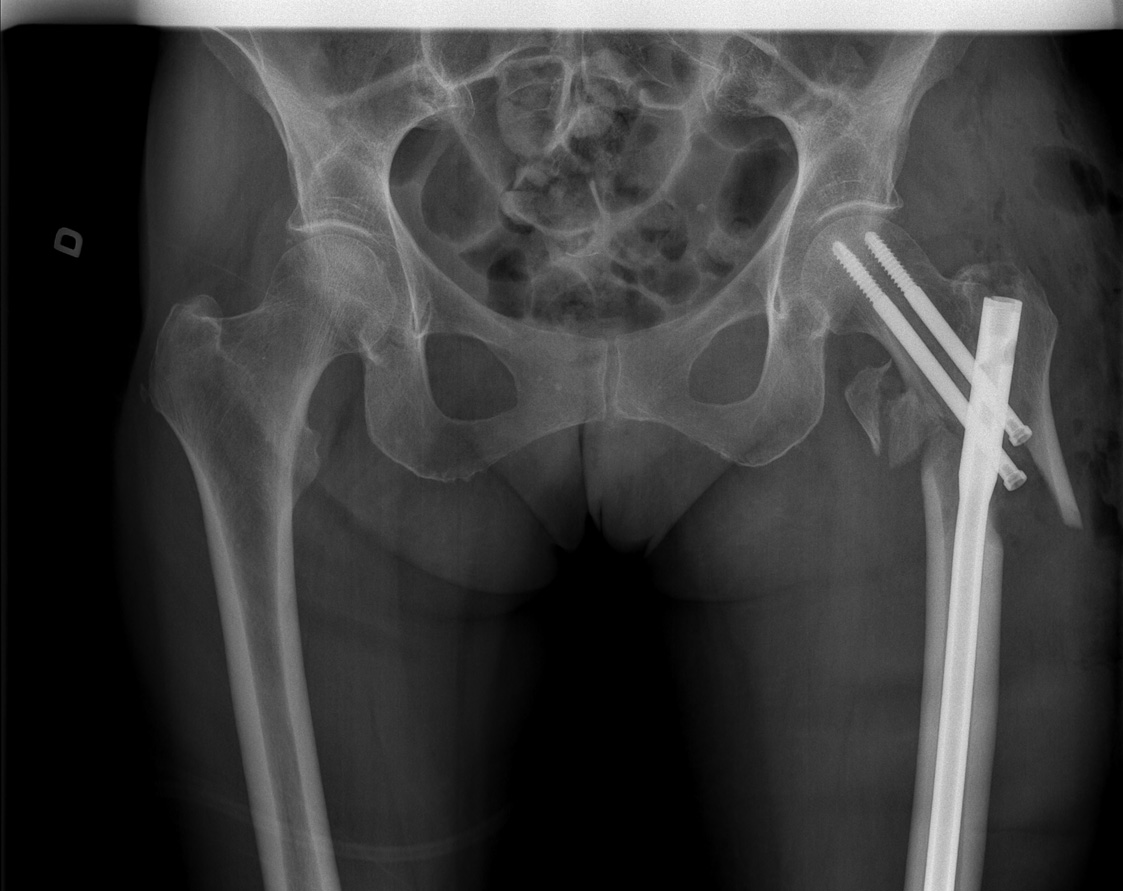

81-year-old female:

Postoperative control of an intertrochanteric fracture.

Open reduction of an intertrochanteric fracture of the reverse obliquity type and internal fixation with a reconstruction intramedullary nail and two transcervical proximal locking screws.

Comminution of the lesser trochanter was not addressed by surgery and is still visible postoperatively.

An angulation and a 26 mm diastasis remain visible at the proximal diaphysis because of the comminution. Alignment of the femoral neck is however adequate.